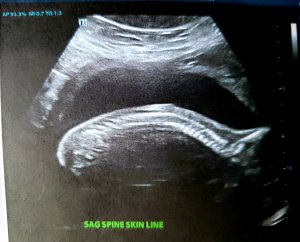

Since it’s now time for soup, Tylenol, and some more sleep, I’ll leave you with snapshots of my tenant’s spine, foot, and hands.